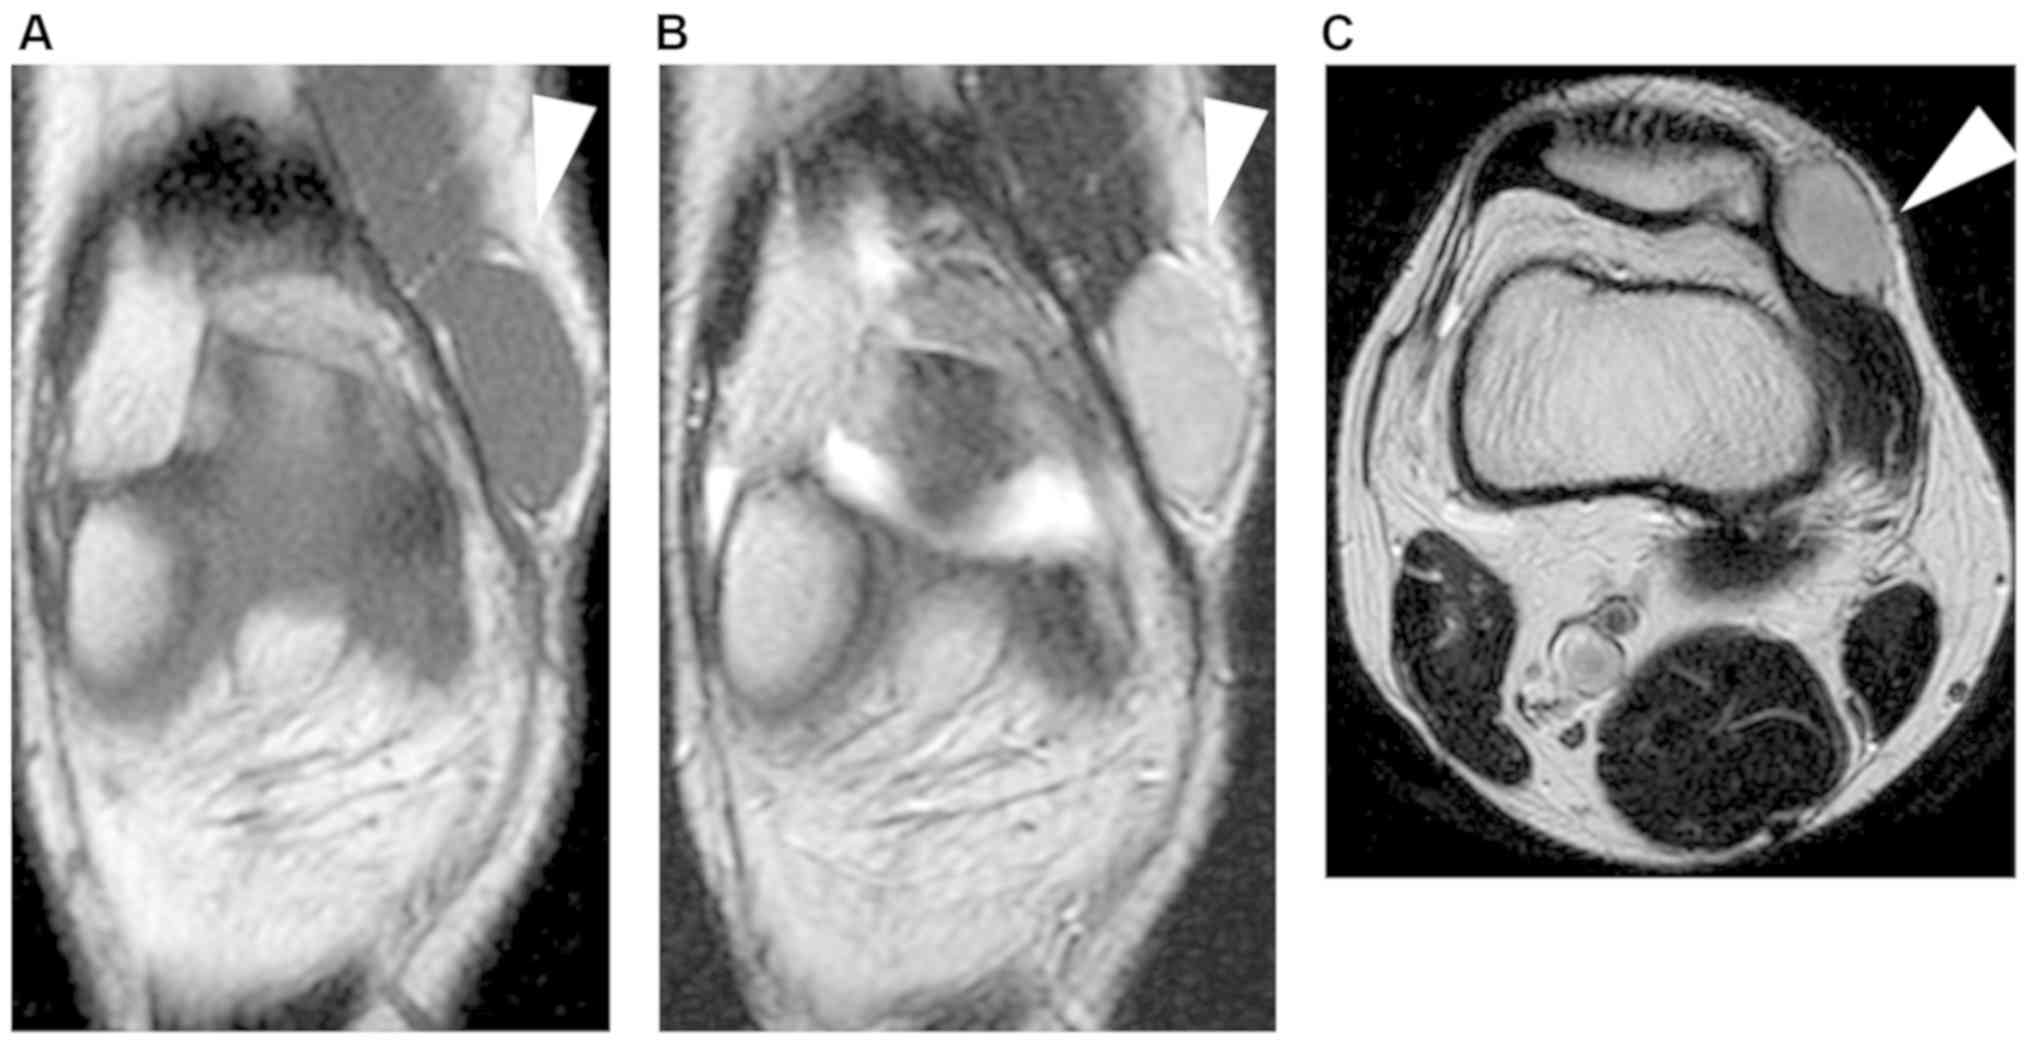

A 16-year-old man presented with pain and a mass on the medial side of his right knee for 1.5 years prior to when he visited his first doctor. The tumor was approximately 3 cm in diameter. He underwent magnetic resonance imaging (MRI) that revealed a circumscribed soft tissue tumor located in the subcutaneous tissue. The tumor had an iso-signal intensity on T1-weighted sequences and high signal intensity on T2-weighted sequences (Fig. 1). The doctor diagnosed the tumor as benign and then performed a marginal resection. However, postoperative histological diagnosis revealed spindle cell sarcoma. The patient was then referred to our hospital for a more specialized treatment. We identified dense freckles and café-au-lait spots on his right inguinal region to the knee (Fig. 2). He had no family history of NF1. The segmental freckles led us to suspect MPNST associated with mosaic localized NF1. Preoperative MRI before additional wide resection showed that a residual tumor appeared to exist adjacent to the patella (Fig. 3A and B). We then confirmed the absence of metastasis and conducted an additional wide resection where part of the vastus medialis, the medial patellar retinaculum and joint capsule, and the patella were resected with the residual tumor. Soft tissue defect was reconstructed with pedicled anterolateral thigh musculocutaneous flap. There was no evidence of residual tumor and surgical margin proved to be negative (R0 resection) (Fig. 3C). The patient did not present with local recurrence and distant metastasis 1.5 years after surgery.

Figure 3.

Preoperative images obtained prior to the additional wide resection and the resected specimen. (A) Axial T2-weighted and (B) diffusion-weighted images (B) are presented. (C) The resected specimen is also presented. White arrowheads indicate residual tumor and/or postoperative inflammatory responses.